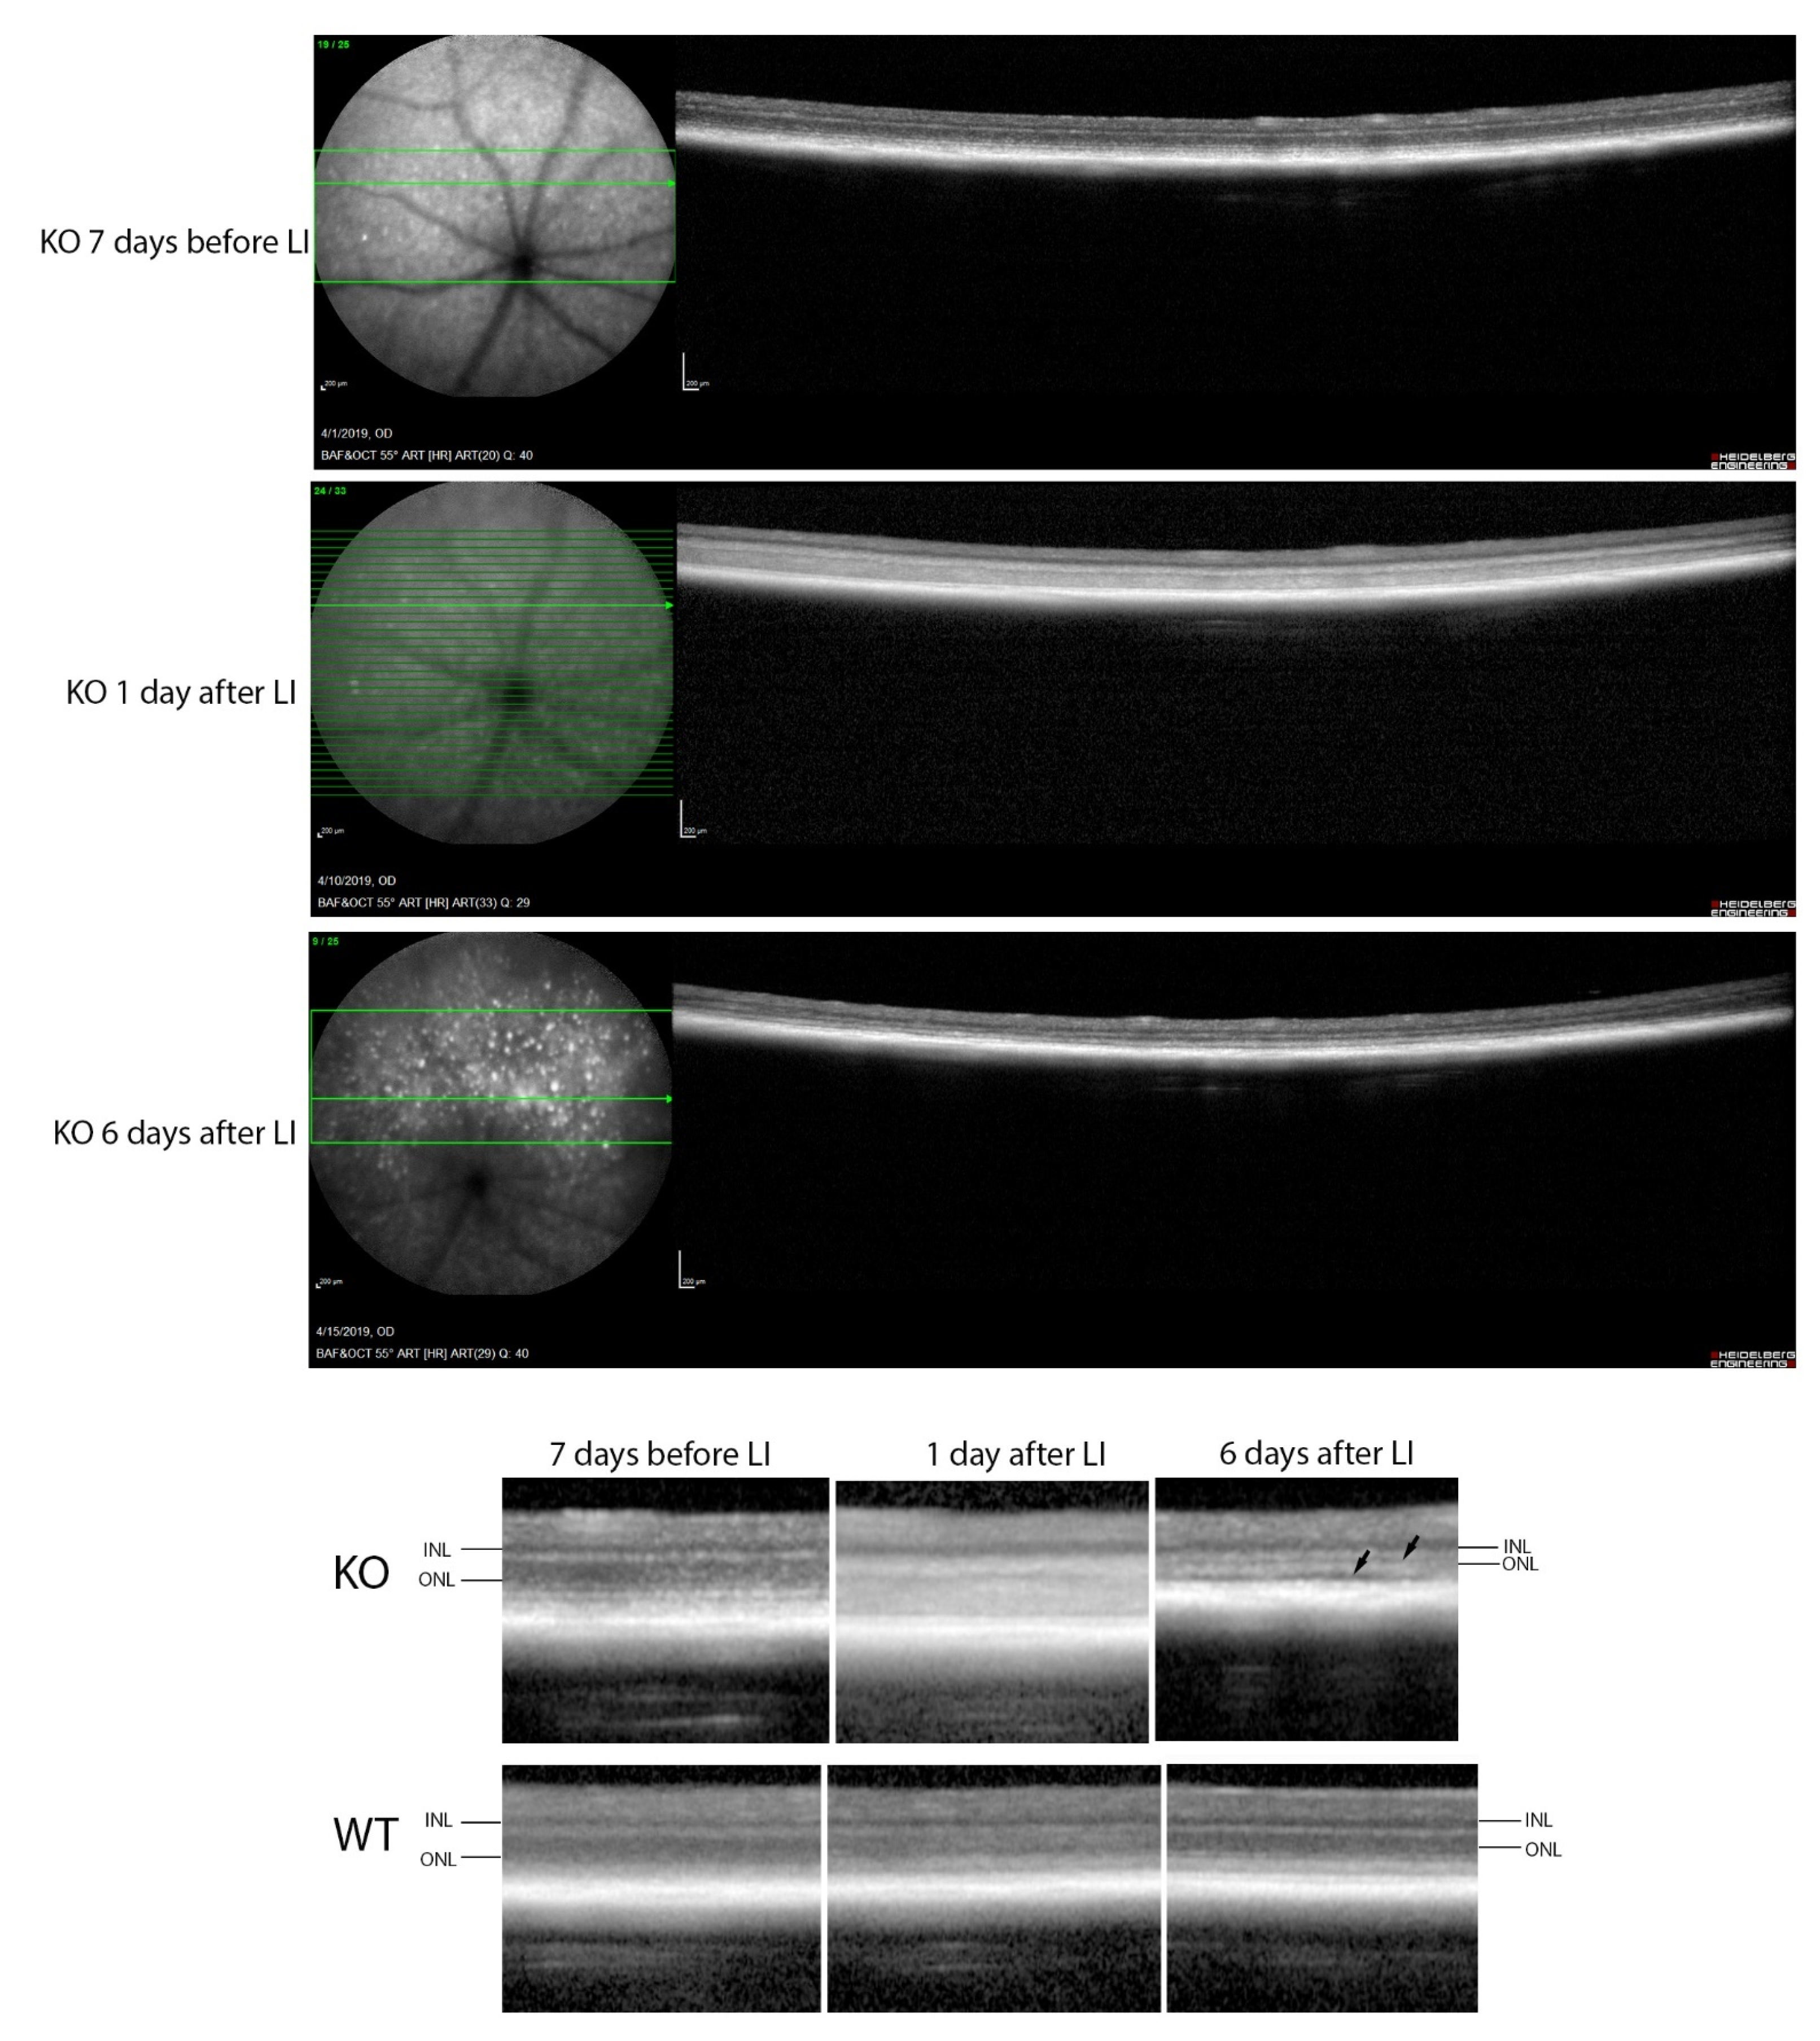

2.5. Decreased RPE Cell Number and Increased Autofluorescent Spots in Cyp4v3 KO Retinas

2.8. High-Fat Diet Stress and Light Injury in Cyp4v3 KO Mice